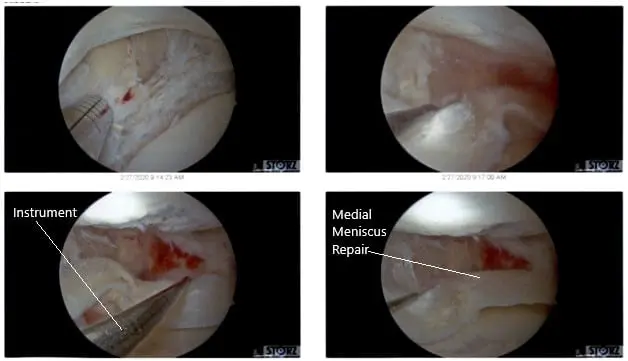

All inside the repair of the medial meniscus was performed using FasT fixers, five curved, two reversed curved in a sequential fashion. Following the repair, the meniscus was found to be stable. Final pictures were taken.

Intraoperative Arthroscopic Views of the left knee.